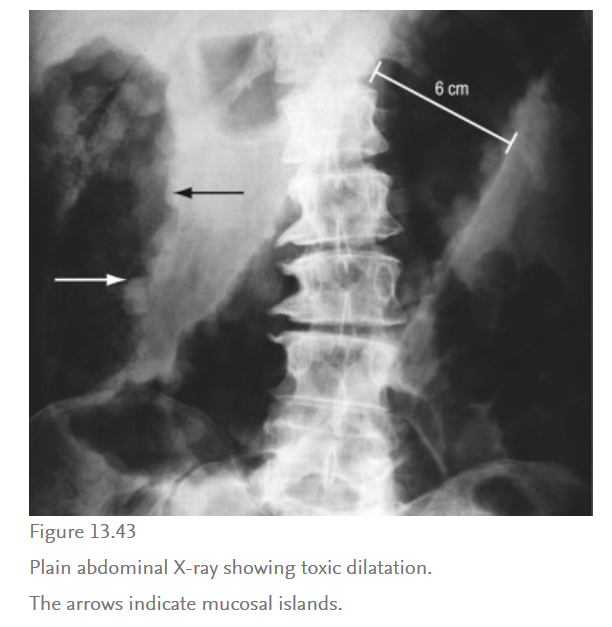

What is toxic megacolon?

What are the complications of UC?

GI - haemorrhage, toxic megacolon, perforation, infection, colonic carcinoma (in those with extensive disease for >10 years), gallstones, PSC (unknown aetioligy, check LFTs every year)